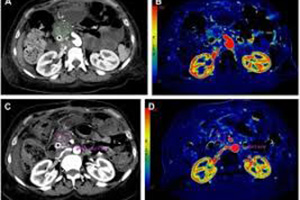

pet-ct

PET - CT

PET/CT, özellikle onkolojide tümörün saptanması, derecesinin belirlenmesi(evreleme), tedaviye...